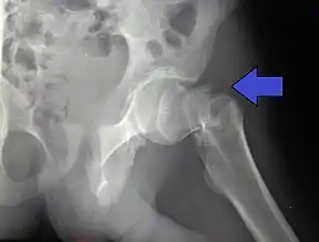

Fractura intertrocantérica en un masculino de 17 años de edad.

Tipos Intracapsular, extracapsular (intertrocantérica, subtrocantérica, trocantérica mayor, trocantérica menor)[2]